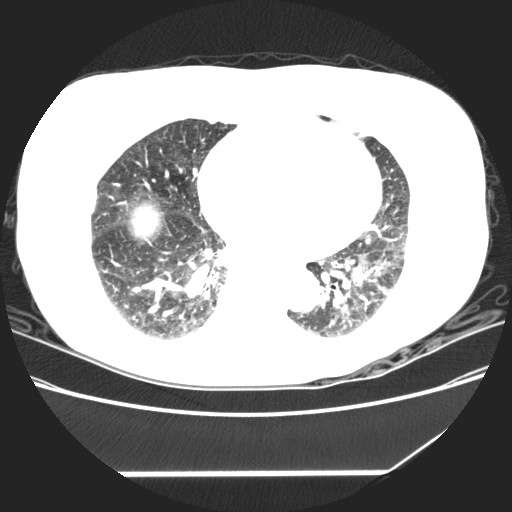

标题: CT24018:女性,62岁,咳嗽4年,无热,胸部CT扫 [打印本页]

女性,62岁,长期咳嗽,既往从事工作有粉尘接触,有高血压病史,110/150mmhg,近日咳嗽加重,脸面浮肿,请大家帮看下,

1、尘肺;2、慢性支气管炎合并肺部感染;3、心影增大(左房、左室大),考虑高血压性心脏病。

慢支并肺部炎症;右肺结核球?主肺动脉、右肺动脉影不宽,右心室不大,不支持肺心病;无心包积液。

右肺无结核球,是肝上缘

1)慢性支气管炎并肺部感染、肺气肿。2)肺间质纤维化。

间质性肺炎,左下肺机化性肺炎。